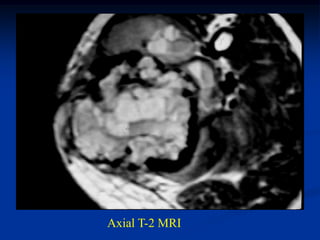

Case #1096

18 year male with

adamantinoma tibia

Axial T-2 MRI